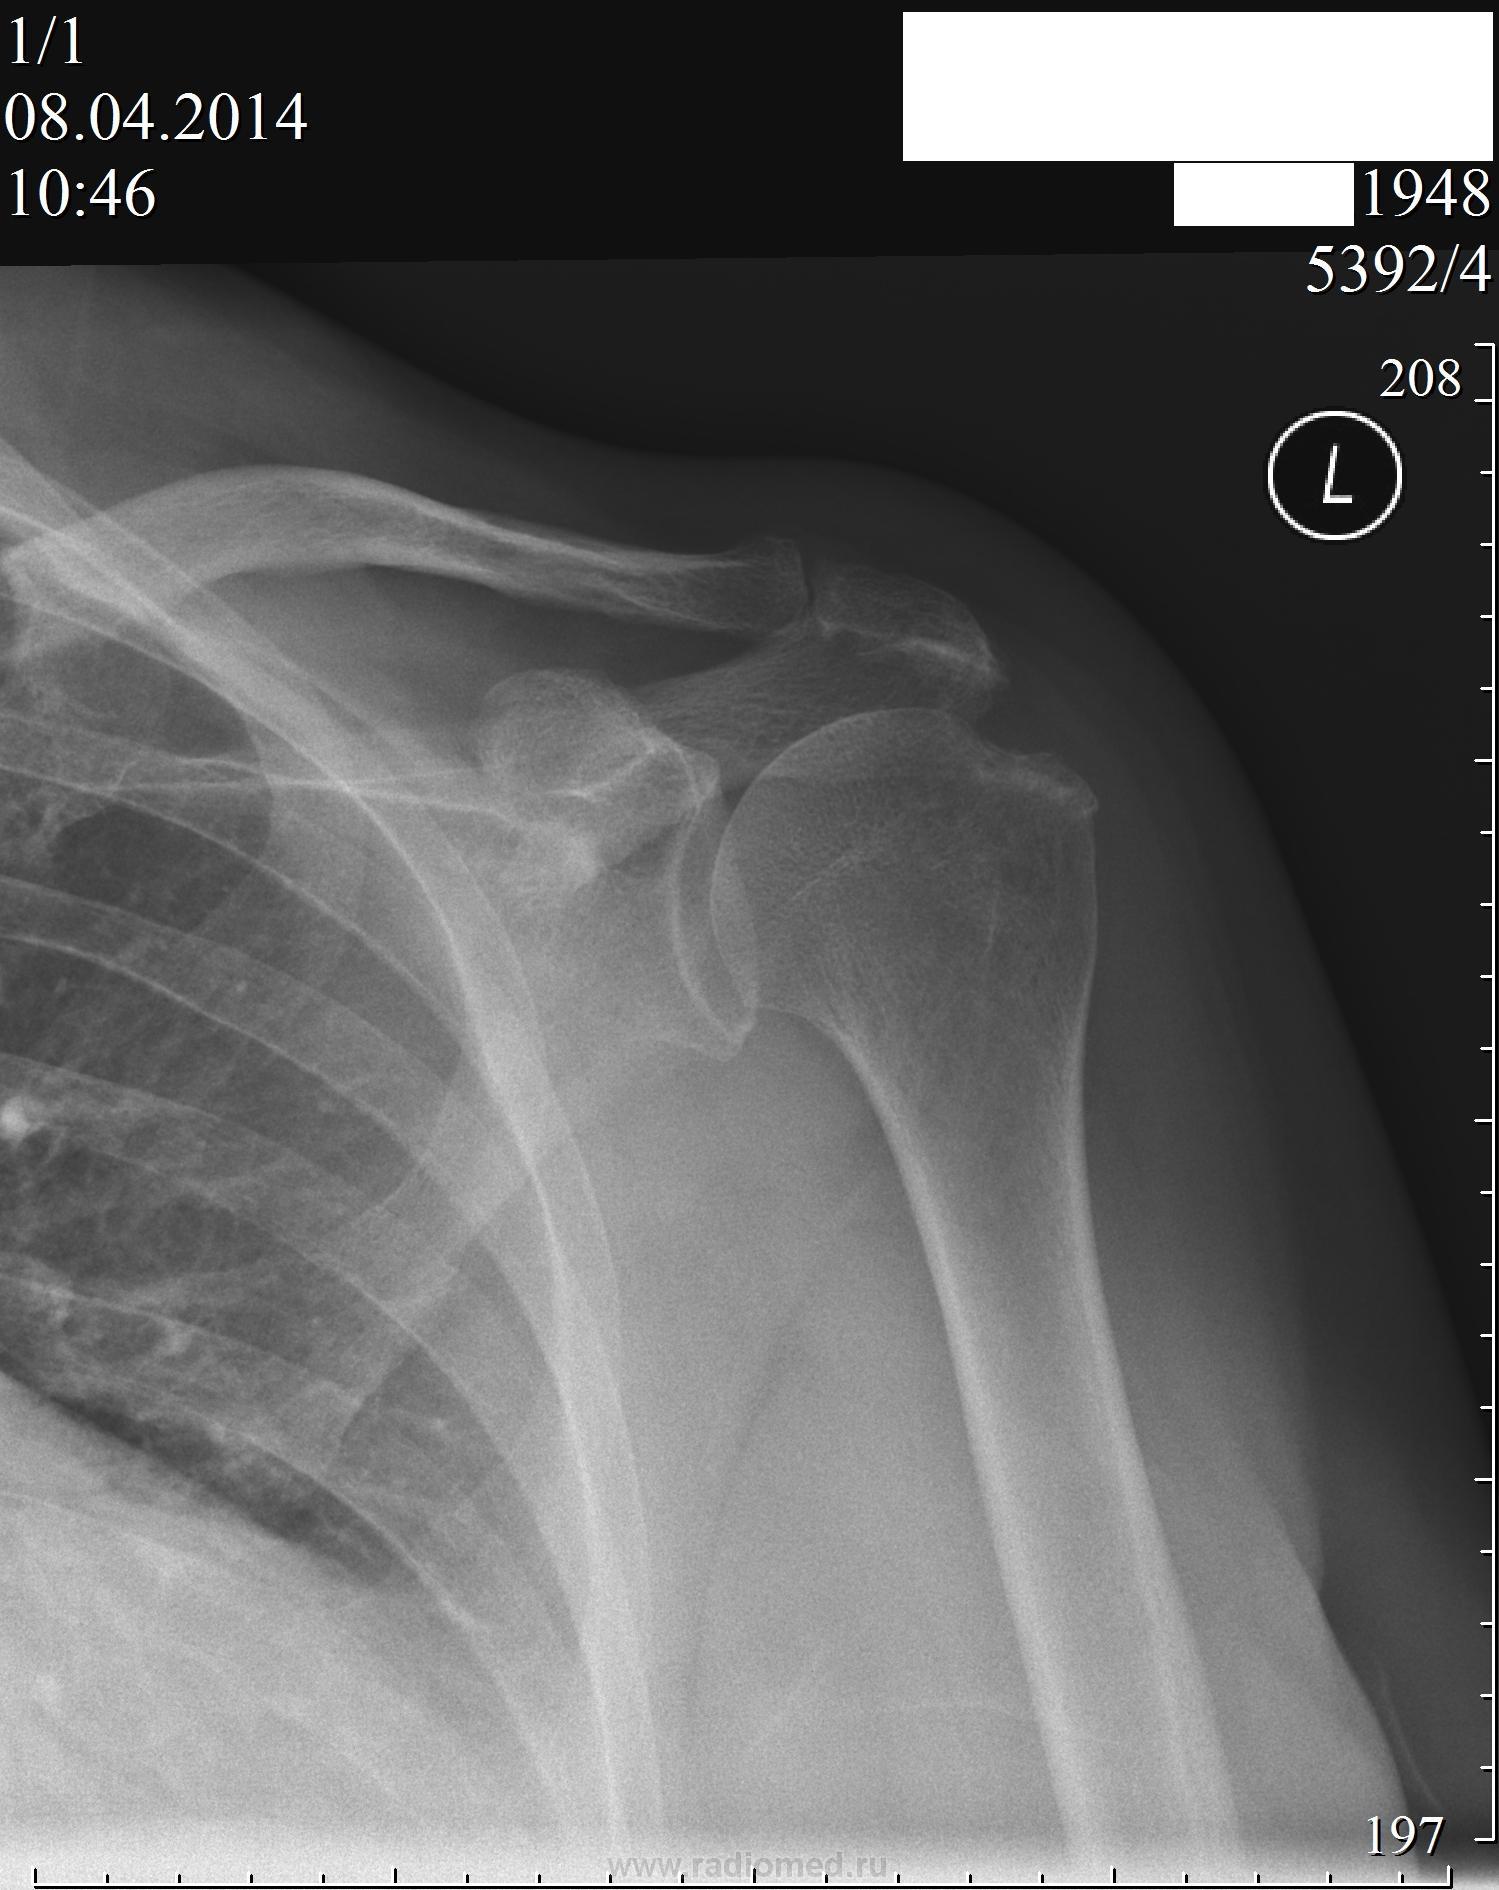

Рентгеновские снимки саркомы плечевого сустава